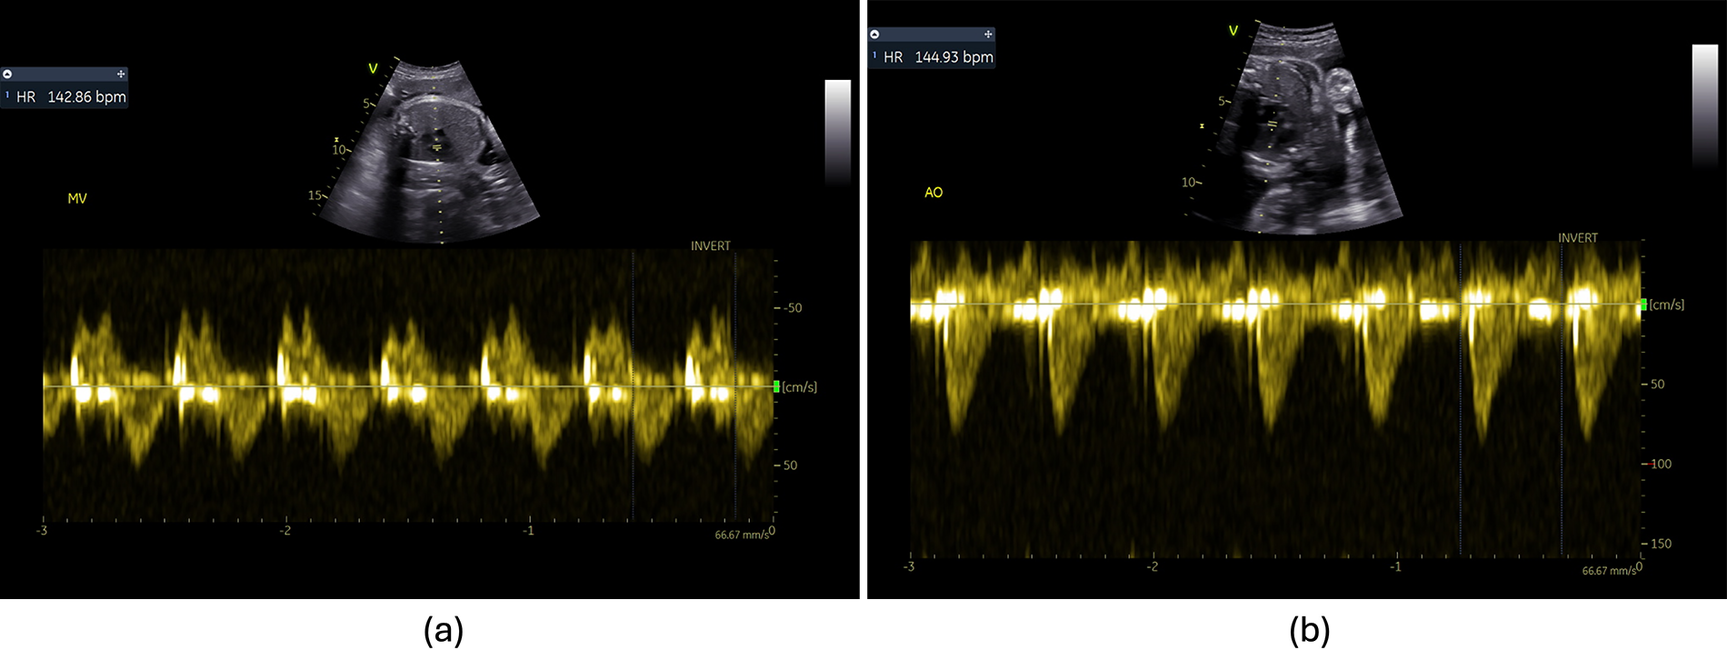

In the medical domain, addressing misclassifications holds significant importance. In this context, we did not add an additional label to the developed DL-based classification models, considering the inherent variability observed in Doppler images and their spectra. With the aim of avoiding additional complexity in the DL models, our strategy focused on the creation of confidence models specific to each Doppler view and dataset. The developed models presented an overall accuracy over 85% across both datasets, consistently maintaining both the FNR and FPR below 15%. However, the LVIO confidence model's accuracy in the FeDoC dataset was notably lower, reaching only 27.8%. The selection of samples used to develop these confidence models was influenced by predictions made in earlier stages of the pipeline. Consequently, the training data for the LVIO confidence model might include Doppler views corresponding to heart valves, such as the MV and AV. Because the LVIO pattern combines elements from both left ventricular outflow and inflow, determining whether to retain or discard an image becomes challenging. Upon review, the identified FP images, classified by an expert as either MV or AV and predicted as LVIO by the XGBoost model, accounted for 1.7% of the test set. These images exhibited evident traces of both AV outflow and MV inflow within the Doppler region (see Figure 7).

Figure 7

False positives of the LVIO confidence models used to detect misclassifications. (a) Image labelled as mitral valve and (b) image labelled as aortic valve.